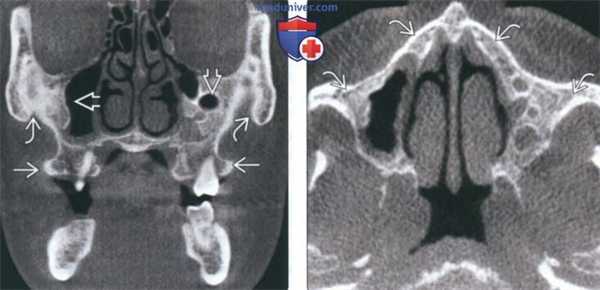

(Слева) На корональной КЛКТ определяется нарушение картины костной ткани у пациента с краниофациальной ФД (КФД) с вовлечением обеих верхнечелюстных пазух и уменьшением их объема. Нарушена морфология альвеолярных отростков верхней челюсти; визуализируются щечные экзостозы, не связанные с КФД.

(Справа) На аксиальной КЛКТ у этого же пациента определяется картина КФД с диффузным нарушением структуры костной ткани верхней челюсти и скуловых костей. Кортикальные пластинки остаются интактными, признаки вздутия на этом срезе отсутствуют.